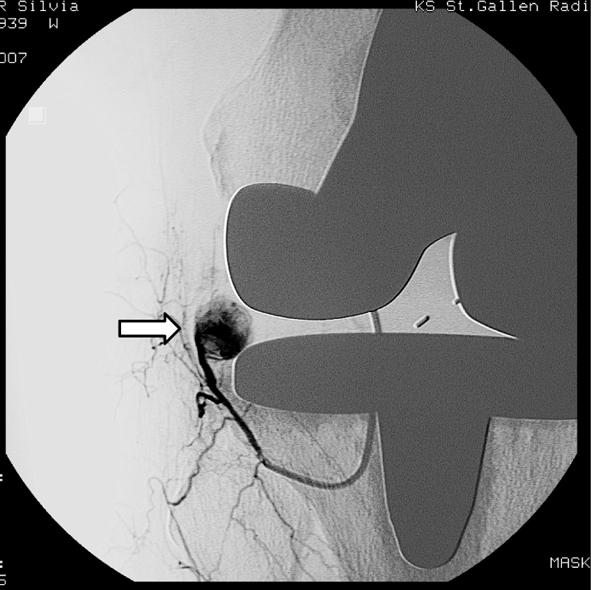

This report describes a case of spontaneous recurrent hemarthrosis of the knee that presented 4 weeks after total knee arthroplasty. Femoral arteriography showed a false aneurysm of a branch of the inferior lateral geniculate artery. Therapeutic embolization of the arterial branch was performed using three platinum coils with good clinical result and good knee joint function. Hemarthrosis has not recurred since embolization.

本报告描述了一例全膝关节置换术后 4 周出现膝关节自发性反复关节积血的病例。股动脉造影显示,膝下外侧膝状动脉分支假性动脉瘤。使用三根铂金线圈进行动脉分支的栓塞治疗,取得了良好的临床效果和膝关节功能。栓塞后关节积血未再复发。